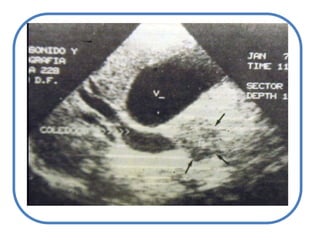

ColestasisIntrahepáticaExtra hepáticaAlteración en el transportadorVías Intra hepáticasHacia el intestinoVías extra hepáticas – pre vesicularesccVesiculares

Anatómica ICTERICIAETIOLOGÍA:CAUSAS POSHEPATICASCAUSAS PREHEPATICASColedocolitiasisAnemia hemolíticaCAUSAS HEPÁTICASCirrosis hepática

Litiasis y estenosis de víasbiliares

Tumores: víabiliar, páncreas o encrucijada